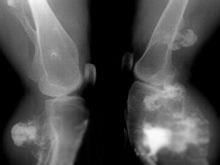

二、影像學診斷

緻密骨瘤顯示隆起,外比光滑,顱骨骨瘤基底寬廣,呈波狀。位內板者則內板增厚。骨密度均勻增加,骨質破壞與骨化程度常不一致。

骨疣常帶蒂,軟骨部可鈣化,呈菜花狀。